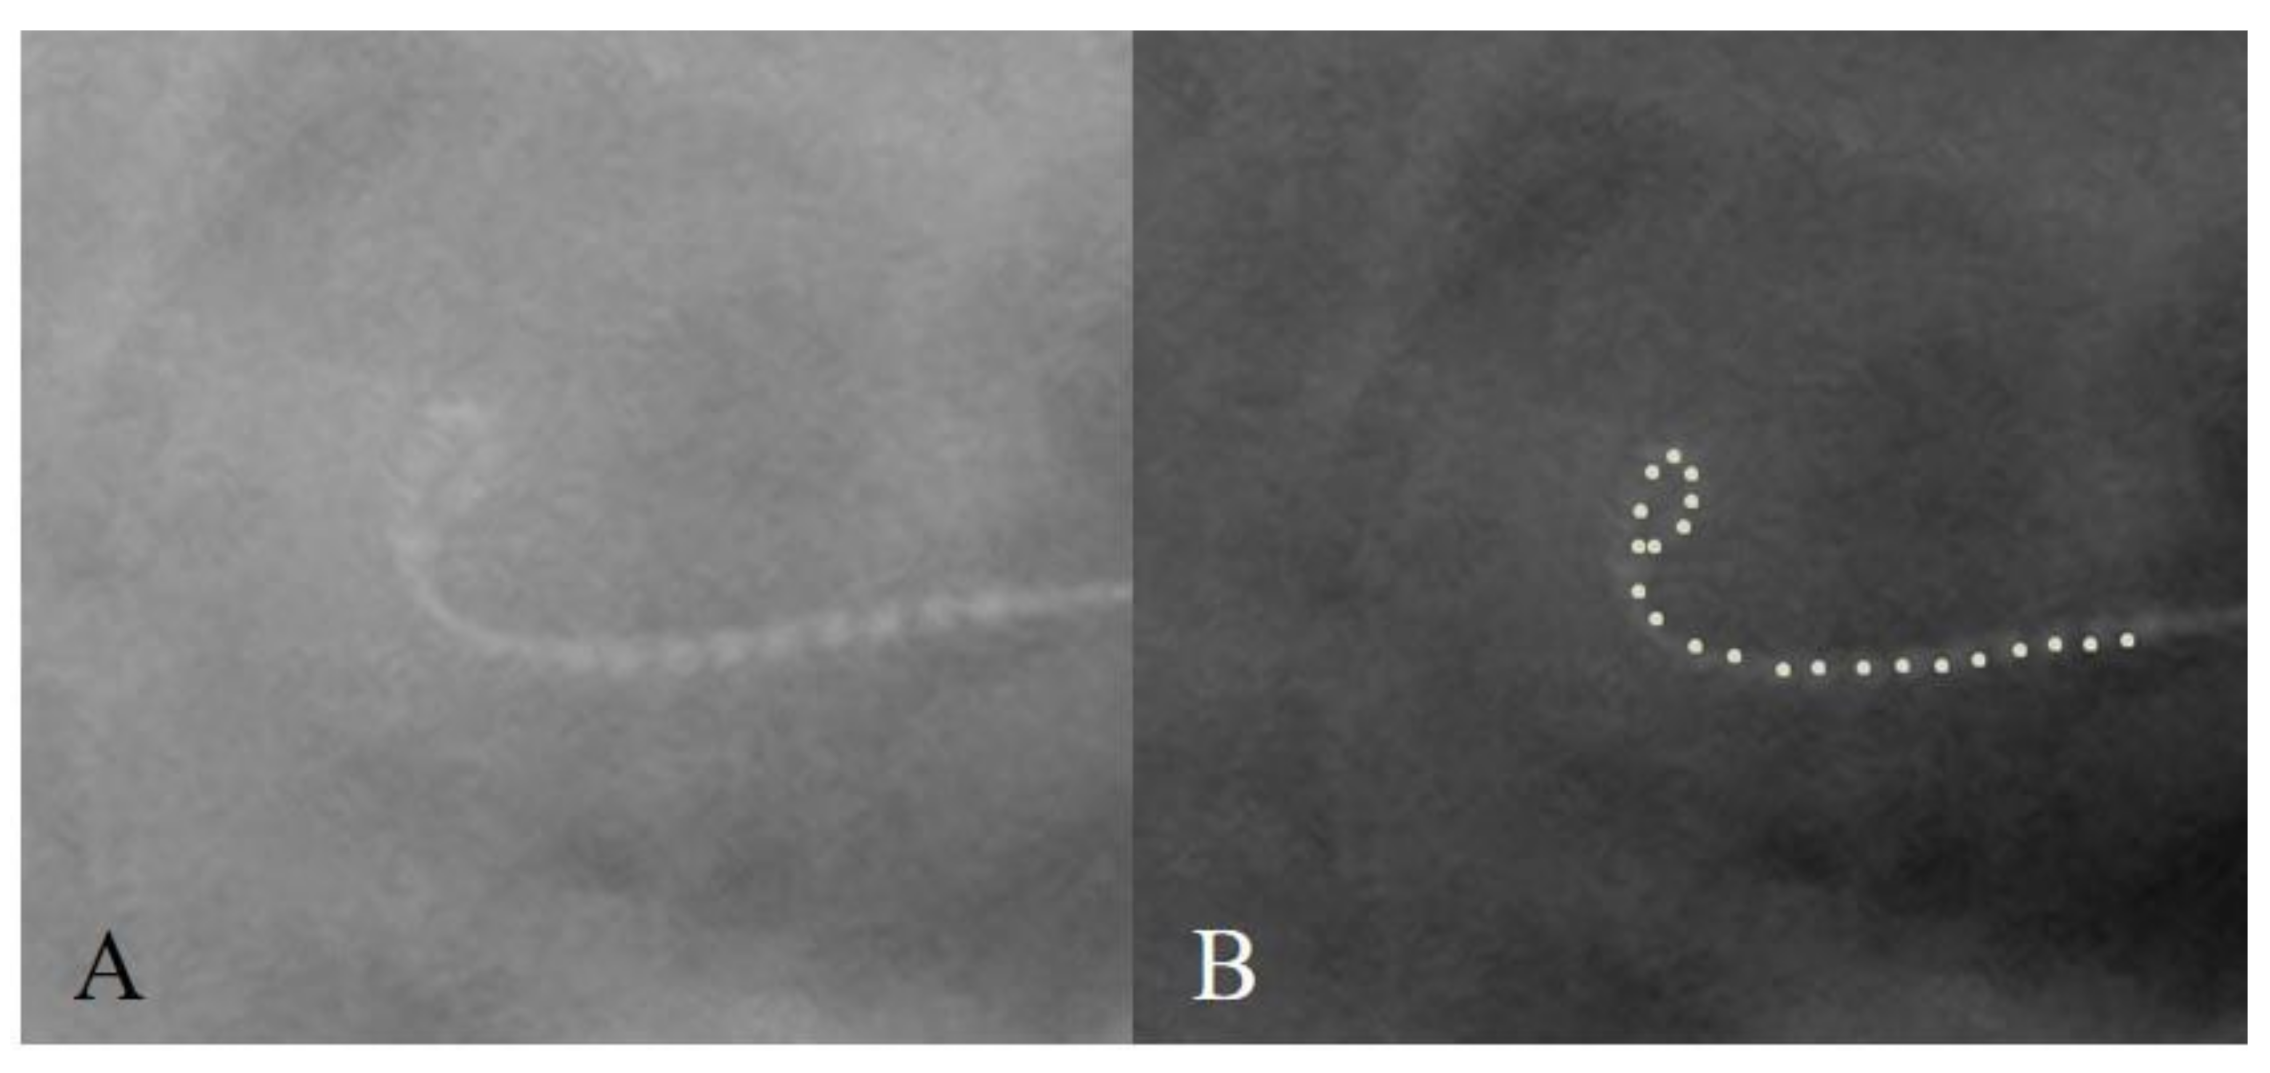

3.4. Case 4: Distal Tip Fold-Over